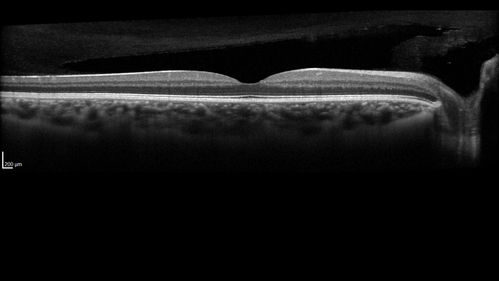

White Retinal Artiole Left eye - Inferotemporal

31 year old female with migraines and headaches for the last 12-13 years. Sometimes she gets the visual symptoms with the migraine. When she gets the migraines the pain is on the left side of her head. She gets the problem a few times a month, sometimes more. They usually last 5-6 hours. She has not had a permanent vision change. When she gets a vision change there are spotty dots of blue neon lights in her vision. With her glasses her two eyes are about the same. VA 20/16 in Each Eye